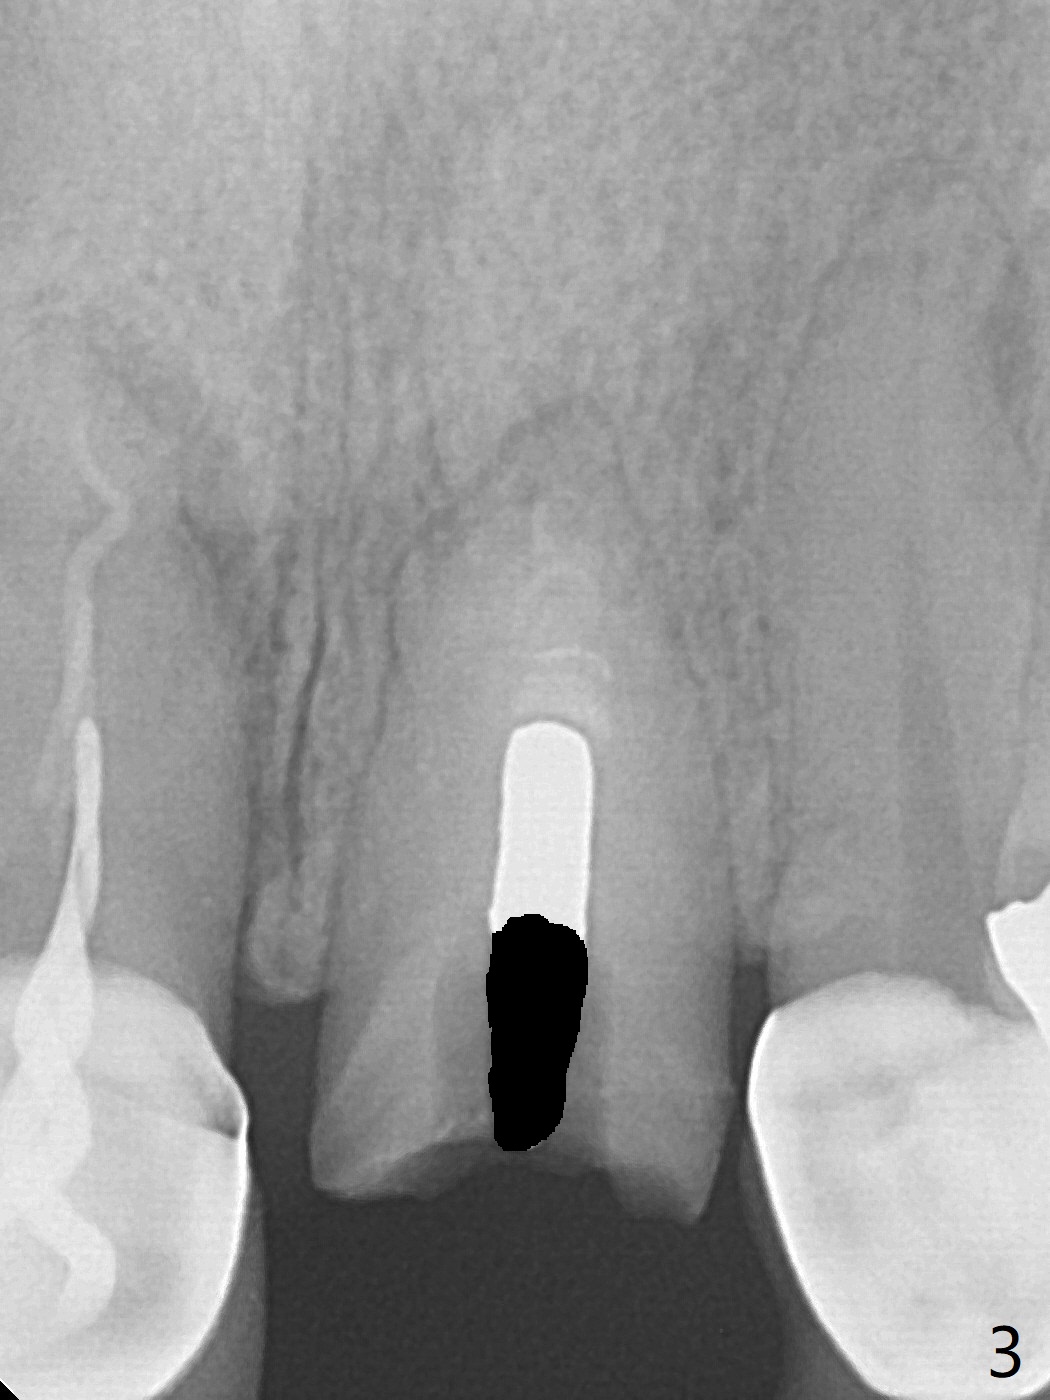

A 51-year-old woman with poor dentition has history repeated dislodged crown and post at #9. Finally the post fracture (Fig.1). After discussion of treatment options, she chooses to save the tooth. Treatment plan is to remove post, possible RCT retreatment, redo post and crown. The post remains stable following lengthy use of Piezo scaler (Fig.2). It appears that Piezo is quite aggressive, removing the tooth structure and the metal. Finally the coronal portion of the post is removed for cast post (Fig.3). There is approximately 2 mm for ferrule effect (Fig.4). The cast post is cemented with RelyX Ultimate and prepared for crown (Fig.5-7).